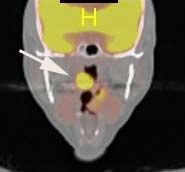

Led by Dr. Eri Srivatsan and Dr. Marilene Wang, UCLA Jonsson Comprehensive Cancer Center members and co-authors of the study, researchers found the link between the protein gigaxonin and head and neck cancer while investigating the chemotherapy drug cisplatin. The drug is successfully able to kill cancer cells by interacting with the protein p16 which is commonly produced in HPV-positive cancers.

“We studied the interaction of p16 in the nucleus of the cancer cell after treatment with cisplatin, and observed how the protein interacted with gigaxonin,” said Wang, professor-in-residence of head and neck surgery. “We found the combination of the proteins stops the cell cycle, allowing chemotherapy treatment to prevent the cell from growing and killing the cancer cell.”

For the study, Wang, Srivatsan and eight colleagues at UCLA also analyzed 103 archival clinical samples from head and neck cancer patients to identify the relationship between p16 nuclear expression and cancer-free survival. They found that patients with cancers with p16 expression had better survival rates than without p16 expression.